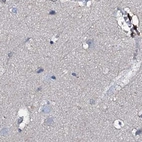

Immunohistochemical staining of human cerebral cortex, colon, duodenum and liver using Anti-ACY3 antibody HPA039219 (A) shows similar protein distribution across tissues to independent antibody HPA048187 (B).